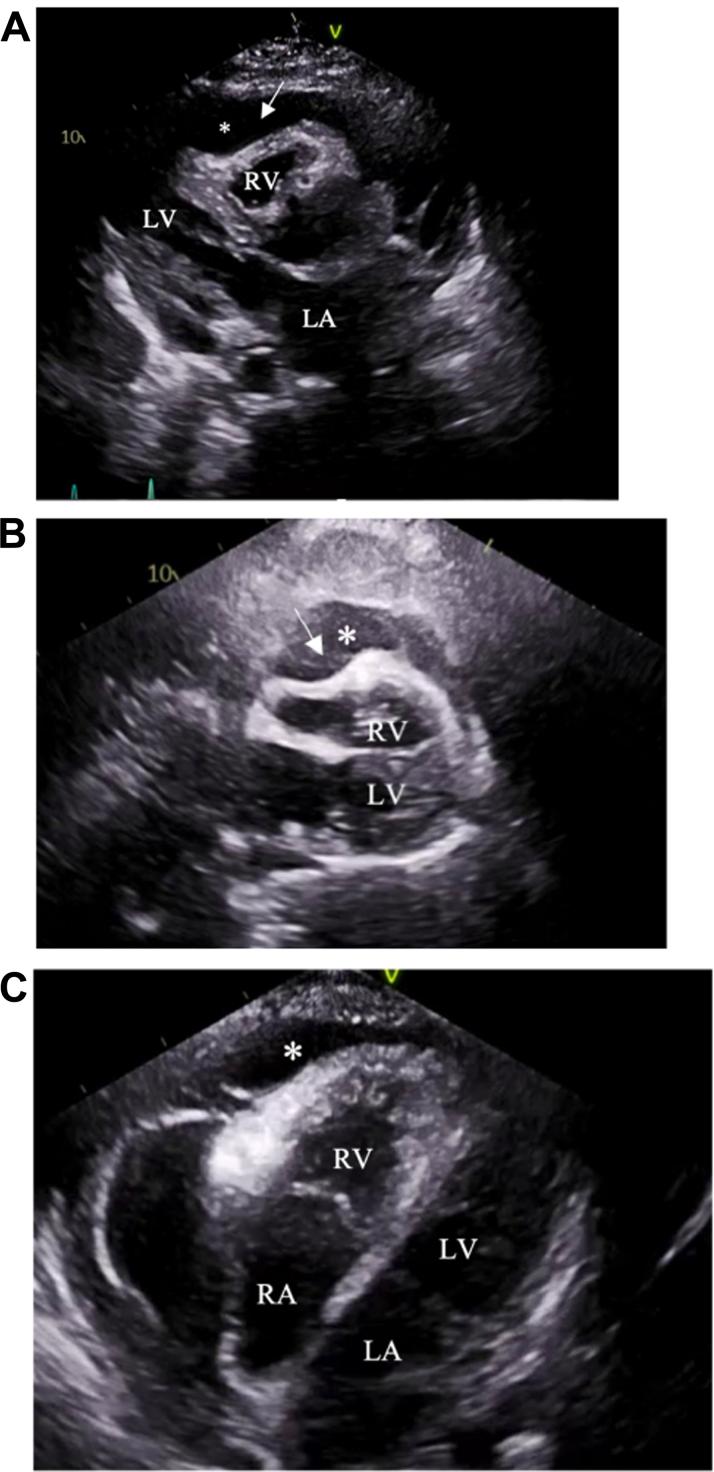

Bispecific therapy has changed the treatment paradigm for multiple myeloma. We report a patient with recurrent malignant pericardial effusions with cardiac tamponade and new atrial fibrillation during treatment, suggesting that new or worsening pericardial disease may be a potential cardiovascular adverse effect of bispecific therapy.

双特异性疗法改变了多发性骨髓瘤的治疗模式。我们报告了一名患者,在治疗期间出现复发性恶性心包积液并伴有心脏压塞以及新发心房颤动,这表明新发或恶化的心包疾病可能是双特异性疗法的一种潜在心血管不良反应。